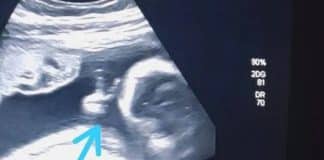

Bebê faz “V” de vitória em ultrassom e pai com câncer vê sinal divino